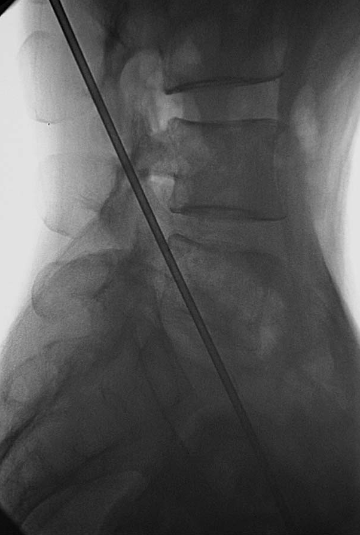

上关节突尖的稍背侧(图11):0.5%利多卡因局麻后用勺状针由穿刺点与额状面呈20°缓缓进针,边进针边注入局麻药,达上关节突尖的稍背侧,抵骨,注入局麻药10ml。

图11 勺状针针尖抵达上关节突尖的稍背侧A.前后位透视;B.侧位透视